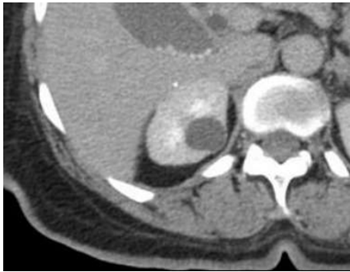

Sobre as imagens a seguir: assinale a alternativa

correspondente à classificação de Bosniak para cada

imagem.

I.

II.

III.

IV.